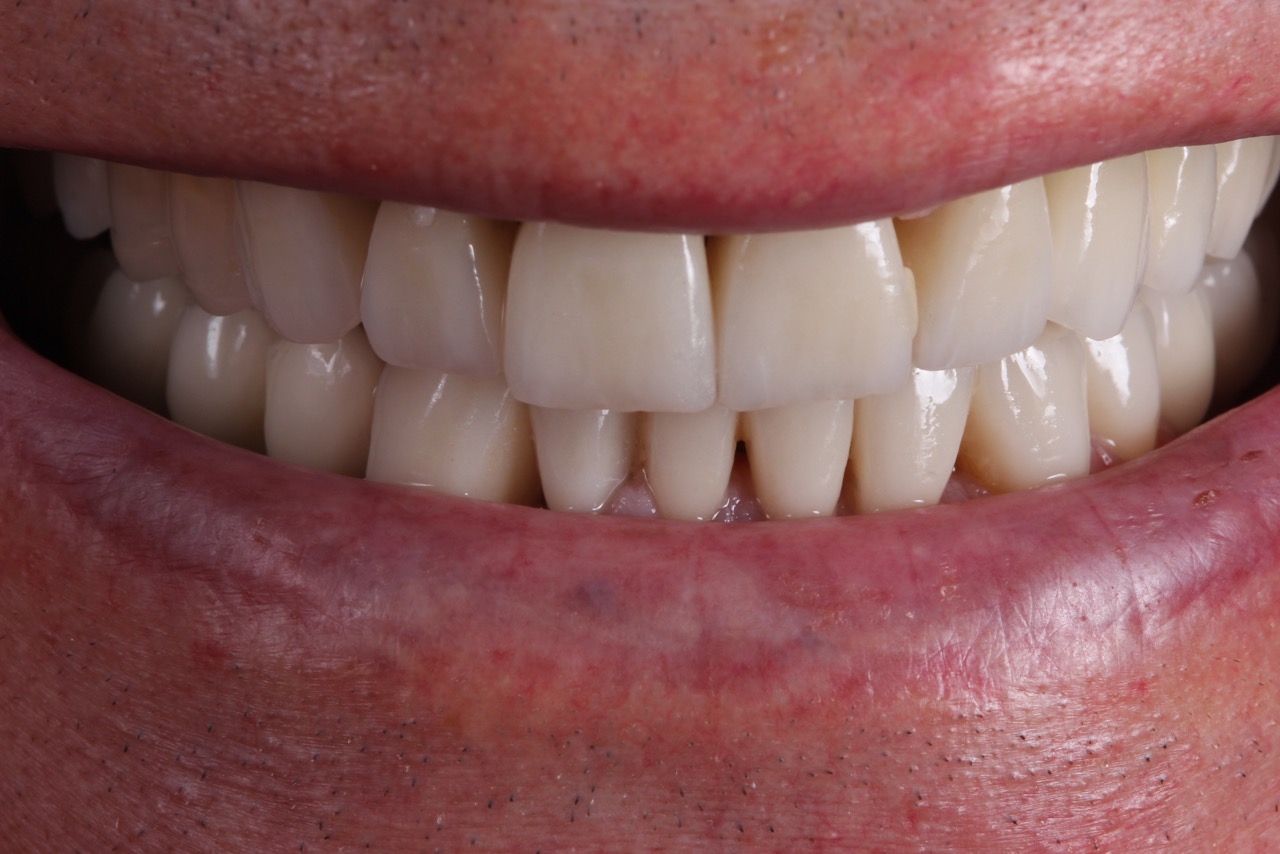

Ejemplo de un caso en paciente con erosiones:

- Después (Cortesía Dra. Eva Berroeta)